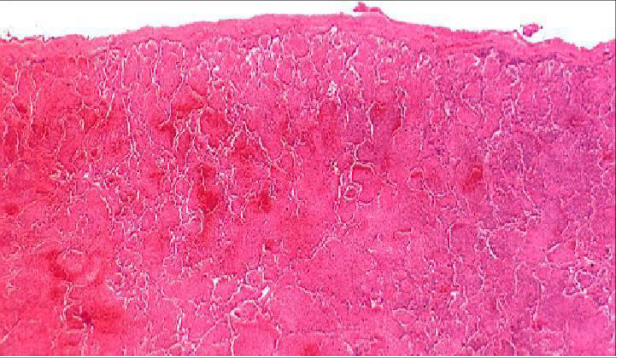

Lobar Pneumonia

Congestion

Red hepatization

Gray hepatization

Resolution